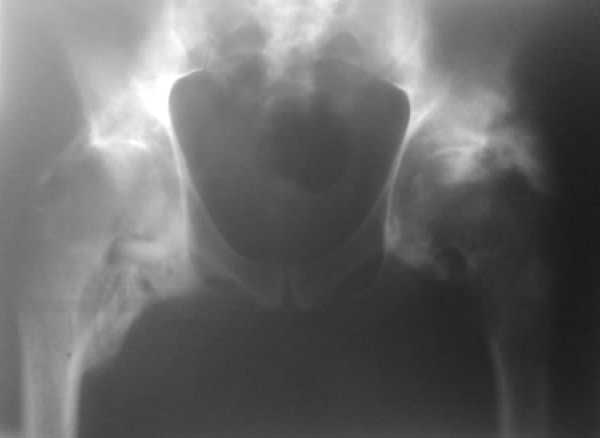

уважаемые коллеги, на консультацию обратился пациент 38 лет

нейрогенной гетеротопической оссификацией. Около полугода назад был

геморрагический инсульт, 1,5 мес в реанимации, был тетрапарез. в

настоящее время имеется внутримозговая гемотома (нейрохирурги решили

"не трогать"), неврологически - с положительной динамикой, регресс до

нижнего прарапареза, АД стабилизировано, соматически тоже с положит

динамикой. Движения в коленных и голеностопных суставах в

удовлетворительглм объеме. ограничение движений в локтевых, плечевых

суставах. Помгите определиться с тактикой в отношении тазобедренных

суставов (движений нет, фиксированное положение в сгибании 170, 0

ротаци). качество снимка -не очень, представляется, что сами суставные

поврехности изменены незначительно. буду благодарен за литературу по

этому вопросу в электронном виде, если у кого есть. Характер

вмешательств (артролиз/THR), сроки, доступы? послеоперационная профилактика?